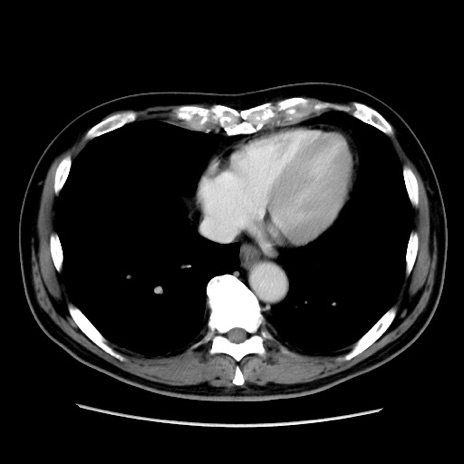

症例16(横断像)

【症例】 70歳代男性

【主訴】 腹痛、嘔吐

【現病歴】 約1ヶ月前より間欠的に腹痛と嘔吐あり、当院消化器内科を受診したところCTで多発する肝臓のLDAを指摘され、精査中であった。以降は消化器症状は安定していたが、2日前より嘔気と腹痛があり、同日より排便・排ガスが消失した。改善認めず、 本日、救急外来を受診した。

【既往歴】 大腸ポリープ切除後。

【身体所見】意識清明・会話良好、BT 36.3℃、BP 127/80mmHg、 P 80bpm、腹部:膨満あり、平坦・軟、上腹部正中および下腹部正中に圧痛あり、反跳痛なし、筋性防御なし。

【データ】WBC 7200、CRP 0.77